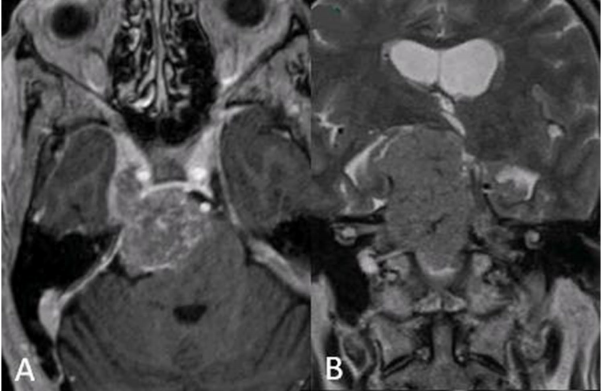

三叉神经鞘瘤是比较常见的非前庭神经鞘瘤,占颅内神经鞘瘤的1 ~ 8%,占颅内肿瘤的0.1 ~ 0.5%。常常发生在中年人身上,也可以发生在任何年龄,包括儿童。...

神经鞘瘤是起源于神经鞘的雪旺细胞的良性肿瘤。它们可以起源于任何外周神经、颅神经或自主神经。三叉神经鞘瘤少见,占全部颅内肿瘤的0.07-0.3%,占颅...